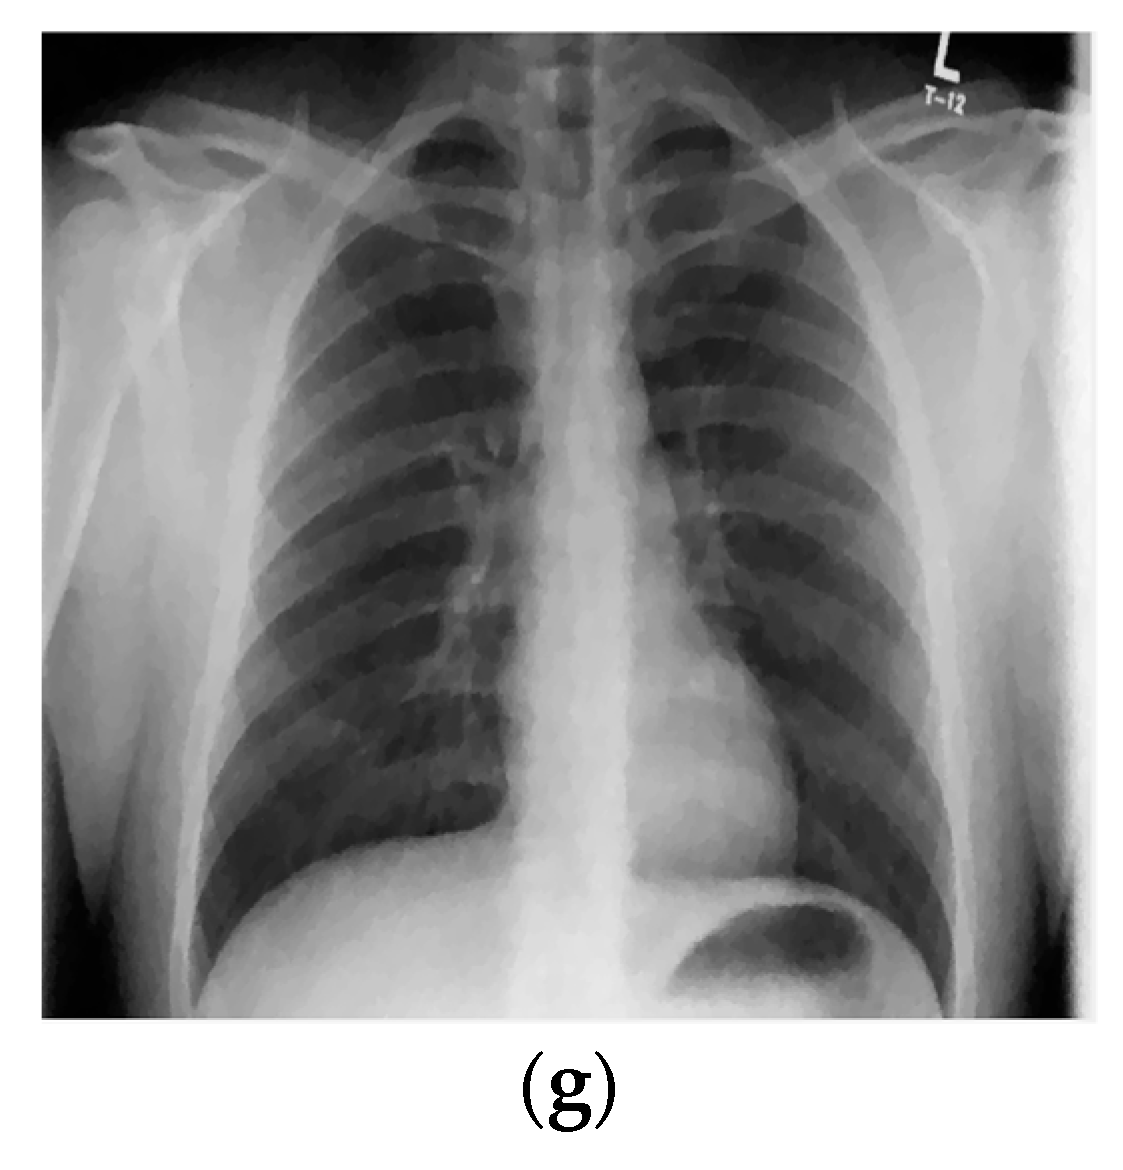

The results for the second test image (chest X-ray image with the resolution 2431 × 1782) are given in Figure 4. Namely, Figure 4a,b shows the noise-free and the noisy image (also corrupted with AWGN with σ = 25), respectively. Figure 4c–e present denoised images obtained using the proposed 2D LPA-RICI algorithm with quadrilateral, octagonal and hexadecagonal regions, respectively.

Figure 4.

Chest X-ray scan. (a) Original noise-free image; (b) Noisy image (AWGN with σ = 25); (c) Image denoised using the 2D LPA-RICI method (quadrilateral region, Г = 1.8, Rc = 0.8); (d) Image denoised using the 2D LPA-RICI method (octagonal region, Г = 1.8, Rc = 0.8); (e) Image denoised using the 2D LPA-RICI method (hexadecagonal region, Г = 1.8, Rc = 0.8); (f) Image denoised using Gaussian smoothing filters; (g) Image denoised using total variation denoising.

The PSNR results for denoised chest X-ray images are found in Table 3. As it can be seen from Table 3, the proposed 2D LPA-RICI method (as it was the case for the shoulder X-ray image) outperformed fixed size 2D filtering in all cases. Furthermore, the RICI based denoising outperformed Gaussian smoothing filters and total variation denoising when quadrilateral and octagonal regions were used.

Table 4 gives PSNR improvements for chest X-ray scan denoised using the 2D LAP-RICI method compared to noisy images and images denoised using the fixed size filtering, Gaussian smoothing filters and the total variation method, respectively. Namely, the LPA-RICI method enhanced denoised image quality, both visually and in terms of the PSNR, by up to 9.40 dB when quadrilateral regions were used, by up to 10.23 dB when octagonal regions were used and by up to 5.25 dB when hexadecagonal regions were used (when compared to the noisy image PSNR). It also outperforms fixed size 2D median filtering in all cases, increasing the PSNR by up to 7.51 dB. In addition, the 2D LPA-RICI method outperformed the Gaussian smoothing filters by up to 5.35 dB when quadrilateral and octagonal regions were used. Furthermore, it also outperformed the total variation denoising increasing the PSNR by up to 3.30 dB (in case of the adaptive 2D quadrilateral and octagonal regions).